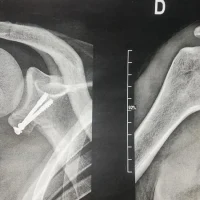

L’instabilité de l’épaule est une condition où l’os du bras supérieur (l’humérus) ne reste pas correctement centré dans la cavité de l’épaule (glène), entraînant une luxation partielle ou complète. Cela peut causer de la douleur, de la faiblesse et des difficultés à bouger l’épaule. Que ce soit dû à une blessure, à des mouvements répétitifs ou à des articulations naturellement lâches,...